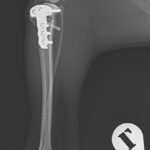

前十字靭帯(完全)断裂に対してCBLO+LSSで対応しました。麻酔下における脛骨ピボット圧迫試験がPositiveであったため、脛骨の内旋矯正のためアンチローテーションスーチャーを追加しています。術中に脛骨の内旋が消失したことが確認されました。前十字靭帯断裂の約30%に術後に脛骨の内旋が残存すると報告されており、術中に不安定性が認められる場合はTPLOやCBLOのみでは脛骨前方スラストは抑制されても、膝の内旋は矯正されないので注意が必要です。